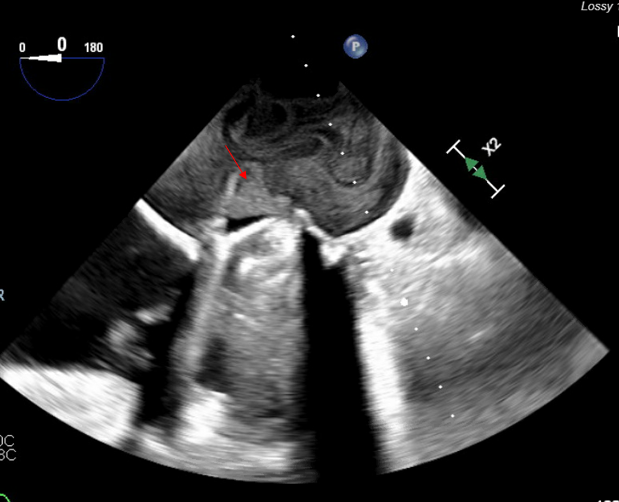

In order to prevent coronary or brain embolization of LAA thrombus, the decision was made to proceed with LAA ligation via the left thoracotomy approach. The patient was then subsequently taken to the operating room for clipping of the LAA with possible cardiopulmonary bypass only if necessary. The LAA was clipped through a left anterior thoracotomy. The patient already had access in her femoral artery and vein for possible institution of cardiopulmonary bypass should it be necessary. A large strand of thrombus was dislodged from the LAA and migrated in the left atrium, obstructing the mechanical mitral valve (Figure 2A-C). The patient was heparinized and placed on cardiopulmonary bypass.